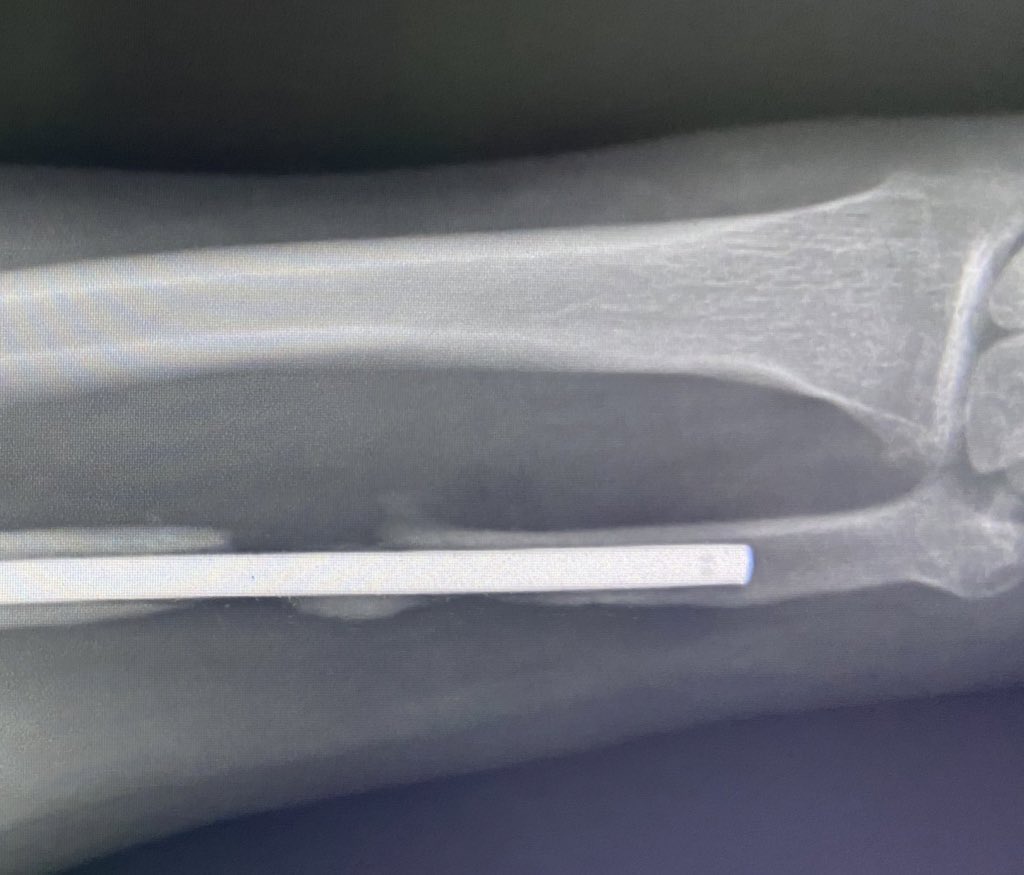

01.11.2022 мені оперують руки, стан яких дуже хуйовий, але не такий поганий як ніг. По лівій руці відкриті переломи кісток, куди встановлюють пластини. По правому плечу зараз є зростання, по ліктьовій кістці без перспективно, немає декількох сантиметрів та навіть натяку на кістковий мозоль, скоріше за все титановий стержень, котрий ввели в кістку, буде зі мною назавжди. Ну і на десерт відмовив променевий нерв, через це ліва кість повисла вниз, нерв було пошкоджено, зараз маю майже повне його відновлення.

По правій руці переломи та опіки трьох пальців. Хірурги дають невтішний прогноз по їх відновленню й кажуть, що скоріш за все будуть їх ампутувати. Перелом кісті, функціонал відновили десь відсотків на 60. А також перелом променевої кістки. Дістали багато осколків. Наклали спиці з якими я тусив два місяці, пальці ми таки зберегли.